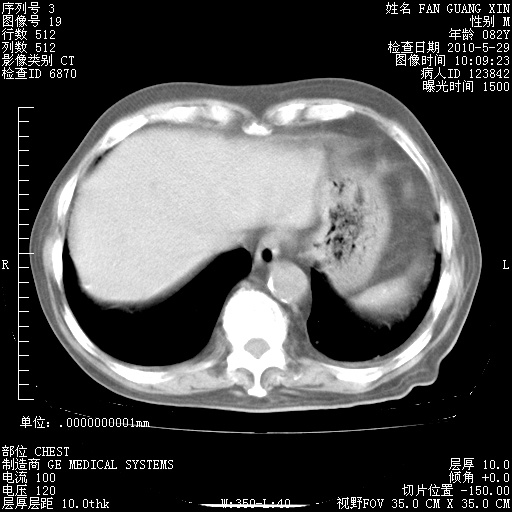

再治疗10天后的肺部CT 纵膈窗

阅读此次胸部CT,肺间质渗出性改变较入院时有吸收。目前从体温、白细胞、中性分叶明显增高,肯定存在细菌感染(发生医院感染哦,若无消化道及泌尿系统等感染的依据,肺部感染可能大)。若你院头孢哌酮舒巴坦钠耐药率较高,同意你的方案,若48小时体温仍高,可考虑使用碳青霉稀类抗菌药物,同时可予超声雾化、注意滴数时加大液体量。白蛋白33.30g/L较低哦,需加强营养等支持治疗。

从白细胞总数和中性比例看好像合并感染。肺部纹理好像比上次多,支气管炎?其他感染?